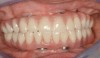

Fig 7. Existing dentition was sound periodontally and reasonably esthetic.

Figure 7

Fig 6. Panoramic radiograph of 56-year-old patient illustrating a number of dental procedures historically.

Figure 6

Interceptive implant therapy may then become a consideration earlier in life to create restorations that will not be subject to the latent effect of dental caries as aging continues. An example is shown in Figure 6 and Figure 7; the panoramic film of a 56-year-old man shows several orthognathic and extensive dental procedures historically. All full-coverage restorations had been replaced for a second time, and, again, all evidenced recurrent caries, but the existing dentition was periodontally sound and relatively esthetic.

The choice of removing a caries-challenged but restorable dentition at a younger age is ethically complex. Ultimately, the decision is the patient's alone based on informed consent of all available options. The removal of a potential lifetime of caries activity that is now more predictable than ever may be a viable option for this high-risk segment of a younger patient base.